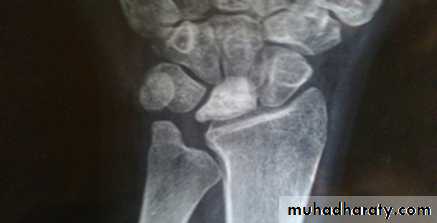

X- ray Radial club handHand congenital deformities :

The lunate bone develop a patchy avascular necrosis. A predisposing factor of Kienbock’s disease may be relative shortening of the ulna.The patient, usually a young adult, complains of ache and stiffness, tenderness is localized to the centre of the wrist on the dorsum, wrist extension may be limited.

Imaging : Typical x-ray signs are increased density and fragmentation in the lunate. The earliest signs of osteonecrosis can be detected only by MRI, later osteoarthritis of the wrist may occur.